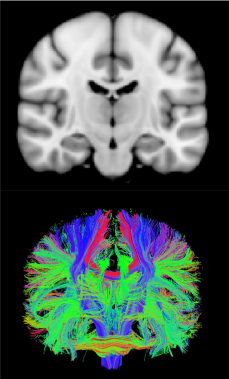

Top: MRI of an average adult human brain. Bottom: Diffusion MRI tractography image.

The “gray matter” of the brain is made up primarily of cell bodies and dendrites of neurons. The “white matter”, on the other hand, consists of bundles of axons which connect different parts of the brain with each other. These types of brain matter are named this way because axon bundles are wrapped in a fatty tissue that makes them appear white compared to the rest of the brain. In the top image to the right, you can see a separation of gray and white matter, with gray matter on the outer surface, or cortex, and white matter in the interior. In the bottom image, the colorful fiber bundles represent white matter pathways. They can span across large regions of the brain, allowing for communication between different areas of the cortex.